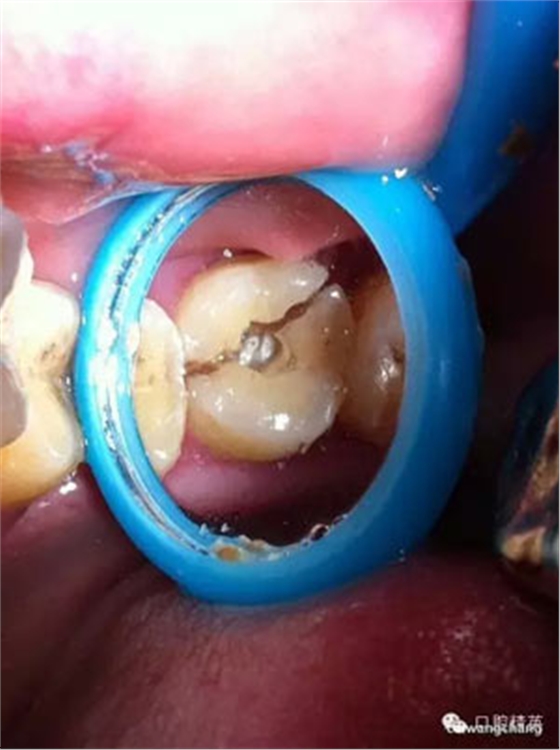

上圖可見該患者的牙斜向裂開,同時沒有做完善的根管治療

玻璃離子墊底

超硬樹脂材料呈啞鈴狀充填,觀察1-2周無反應給予牙體預備烤瓷冠修復